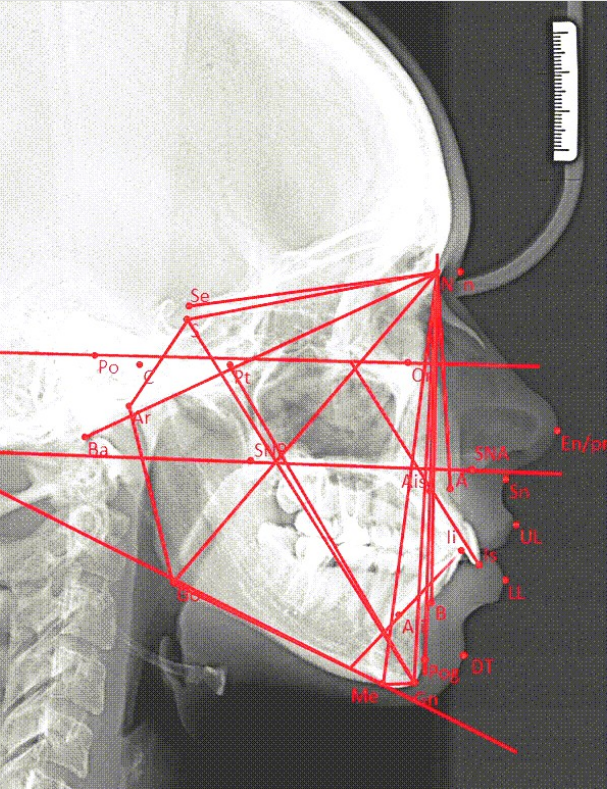

Research and diagnostics of patients in orthodontic treatment have become the subject area for the development of applied software [9]. There are many classifications of anomalies studied in orthodontics: jaw size anomalies, anomalies in the position of the jaws in the skull, anomalies in the ratio of dental arches, anomalies in the shape and size of dental arches, anomalies of individual teeth [10, 11]. An approach called cephalometric radiological image analysis, at the planning stage of treatment provides mathematical values for further analysis and diagnosis, such as jaw length and angles of inclination. The use of applied software based on the concept of using convolutional neural networks should significantly speed up the process of cephalometric analysis of radiological images, since the process itself is often performed manually or in a graphic editor without the ability to automatically obtain decoding [12]. The methodology for using convolutional neural networks has been studied earlier, therefore, at the software development step, we assign value to the parameters of the software being developed based on the neural network model [13].

An approximate view of the result of decoding the image is shown in Fig. 1.